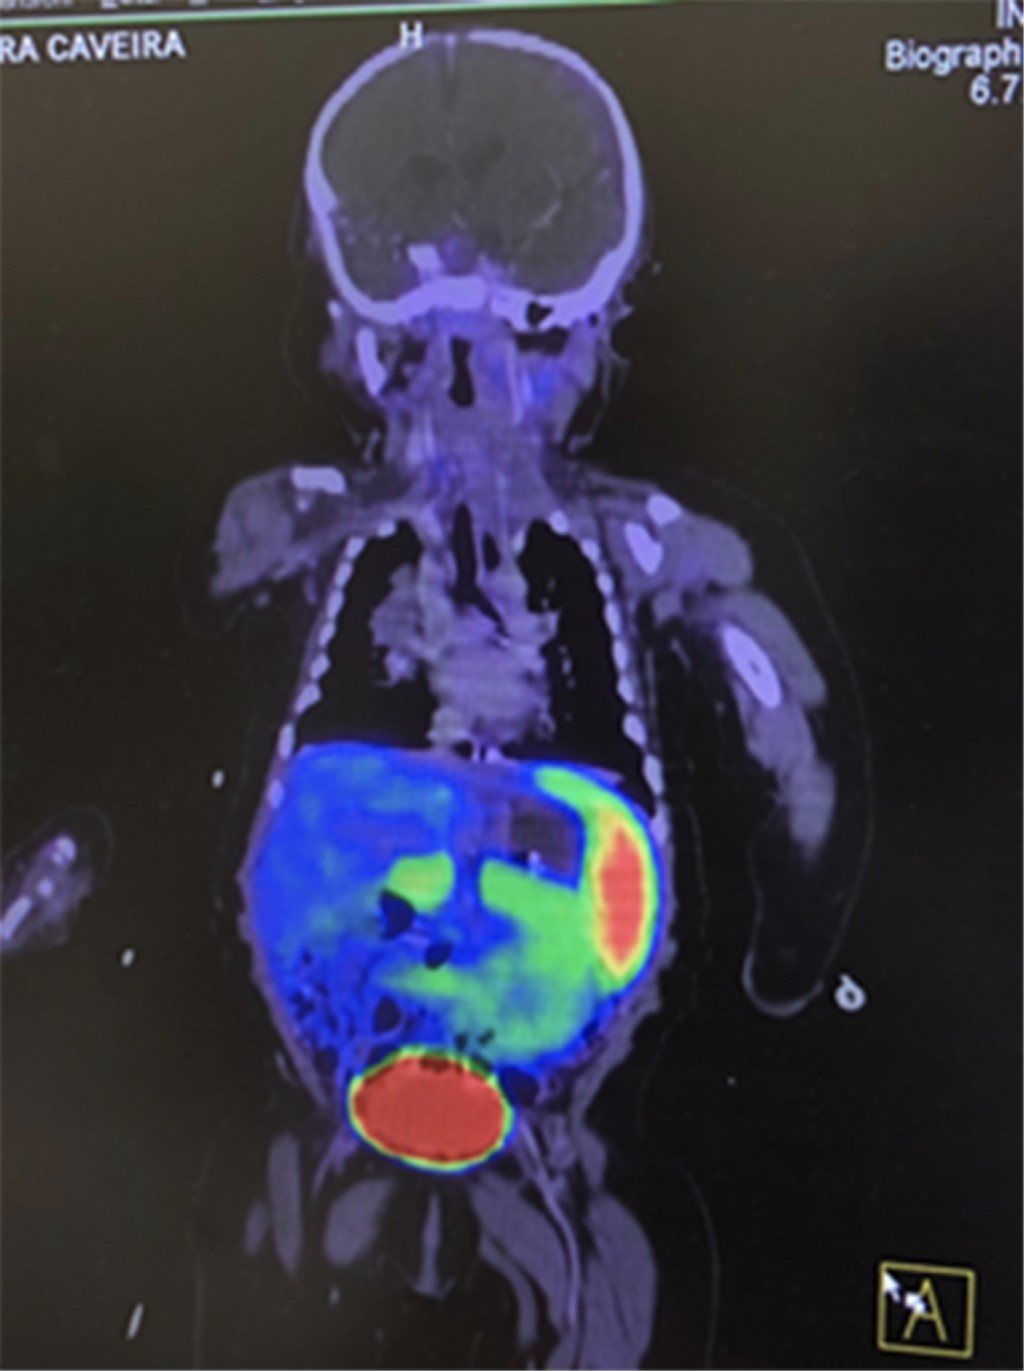

Inicia su padecimiento a las 4 horas de vida con hipoglucemia de 11 mg/dL que amerita aporte de glucosa-kilo-minuto (GKM) de 13-14 mg y al cuarto día de vida presenta crisis convulsiva tónico-clónica generalizada con bradicardia y cianosis. Ingresa al Instituto Nacional de Pediatría referida del Hospital General de Cancún el 7/06/18, se inicia manejo con octreotide de 3.1 μg/kg/dosis cada 6 horas y se le realiza tomografía por emisión de positrones (PET, por sus siglas en inglés) (Figura 2) con probable hiperinsulinismo difuso; se observa evolución tórpida con mala respuesta al tratamiento, por lo que se programa para pancreatectomía (Figura 3).

Figura 2